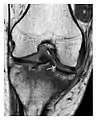

Proximal femoral fractures usually occur in osteoporotic patients, and their signs include subtle neck angulation, trabecular angulation, and subcapital impaction line. A frog-leg lateral view may be helpful if the greater trochanter is short enough. However, positioning can be difficult because of hip pain. In patients with strong suspicion of proximal femoral fracture and negative radiographs, MRI limited to coronal T1 W images and scintigraphy can be highly valuable (Figures 13 and 14). Such an option, with limited examination time, is cost-effective and allows reliable exclusion or confirmation of the diagnosis, preventing an unnecessary stay at the hospital or delayed treatment. Moreover, MRI helps to detect soft tissue abnormalities which are more frequently seen in femoral, acetabular, and pubic injuries than sacral lesions. Concomitant fractures are also frequently seen in typical pelvic sites.[1]

Figure 13: Partial osseous avulsion of the gluteal muscles at the greater trochanter in a 59-year-old man who presented with the right hip pain without a history of trauma. Lauenstein view and anteroposterior and radiographs (not shown) did not show an obvious fracture line or disruption of bony contours in the acetabulum or the right femoral neck. (a) Coronal T1-weighted MRI displays an incomplete fracture line extending partially from the greater trochanter (arrow). (b) Coronal short tau inversion recovery MRI shows heterogeneous hyperintensity in the same region (arrow) as well as hyperintensity within the gluteus medius and minimus muscles (arrowheads) consistent with tissue edema and hematoma.[1]